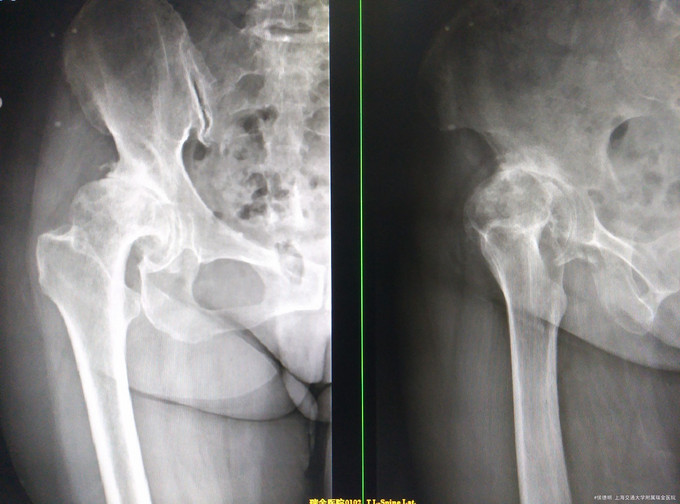

右侧髋关节疼痛10年 近10年来患者走路时右髋关节疼痛伴活动受限,【骨盆正位片】示:右侧髋臼变浅,髋臼边缘骨质密度增高,右侧股骨头变扁外移,骨质密度不均匀,关节面不光整,在关节面下见不规则高密度影,其间小囊状低密度灶,为进一步诊治,拟“右髋DDH”收入院。 患者自发病以来神清,精神可,夜眠胃纳一般,体重无明显下降

神清,精神可,双下肢无明显肿胀,右侧髋关节局部轻压痛(+),叩痛(±),活动受限,4字征(+),轴向叩痛(—)。 X片提示右侧髋关节发育不良,髋关节退行性病变